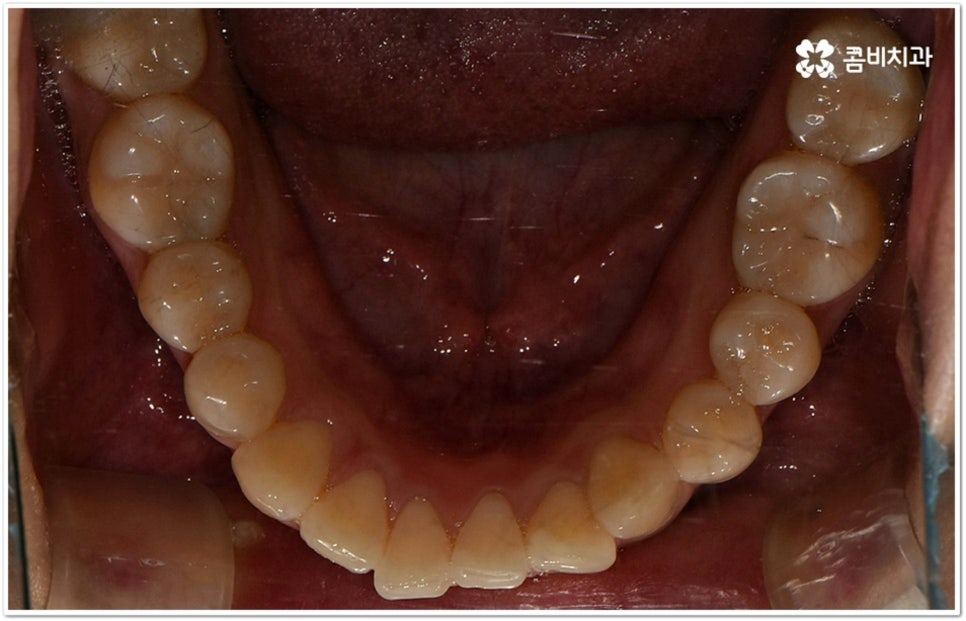

사실 치아가 많이 겹쳐서 삐뚤빼뚤하면 보기에도 좋지 않고 사이사이에 음식물 찌꺼기가 끼어서 충치 같은 구강 질환도 더 자주 발생할 수 있기 때문에 환자분들의 입장에서도 교정 치료를 고려하시는 경우가 많지만, 아주 살짝 덧니가 있을 때는 교정에 대해서 별로 심각하게 생각하지 않으실 수도 있는데요. 이런 덧니는 사람에 따라 오히려 매력 포인트가 될 수도 있기 때문에 스스로 느끼기에 문제가 아니라고 생각한다면 반드시 교정 치료를 해야 하는 것은 아니지만, 만약 입을 벌렸을때 잘 보이는 앞니, 송곳니 등이 덧니라서 웃거나 말을 할 때 신경이 쓰이거나 자기도 모르게 손으로 가리는 습관이 들 정도로 자신감이 떨어진 경우라면 한 번쯤 고려해 보셔도 좋을 거예요. 특히 위아래 맞물림에 문제가 없고 구조적인 부분과 관련된 원인이 크지 않다면 덧니부분교정 을 통해서 보다 빠르고 간편하게 개선이 가능한 케이스도 있기 때문에 꼼꼼한 검진을 통해 자신의 상황이 어떤지부터 알아보시길 권유드리고 있습니다.

덧니의 원인에는 여러 가지가 있는데 대표적으로는 유치가 너무 일찍 빠져서 영구치가 제대로 자리를 잡지 못했거나 턱뼈의 크기와 치아 크기가 조화를 이루지 못하는 경우 등 공간이 부족한 상황을 생각해 볼 수 있어요. 덧니는 주로 송곳니가 가장 흔하나, 치열이 공간이 부족할 경우 이론적으로는 어떤 치아라도 덧니가 될 수 있어요. 이때 원인과 정도를 꼼꼼하게 파악하여 만약 해당 부위만 부분 교정이 가능하다면 덧니부분교정 치료를 할 수 있는데요. 덧니부분교정 을 이용하면 원하는 부위에만 브라켓을 부착하여 치아 이동을 시키기 때문에 전체 교정에 비해서 간편하며 치료 기간도 6~8개월 정도로 줄어들고 통증도 많이 감소될 수 있습니다. 비용적인 부담도 덜하며 (삐뚤어진 정도나 상태에 따라 다르겠지만) 보통 덧니부분교정 의 경우 비발치 과정으로 진행되기 때문에 환자분들의 입장에서는 덧니부분교정 을 많이 선호하시는 편이라고 할 수 있어요. 상황에 따라 미니스크류, 치간삭제, 악궁확장장치 등 환자에게 맞는 비발치 방법을 이용하여 도움 받을 수 있습니다.